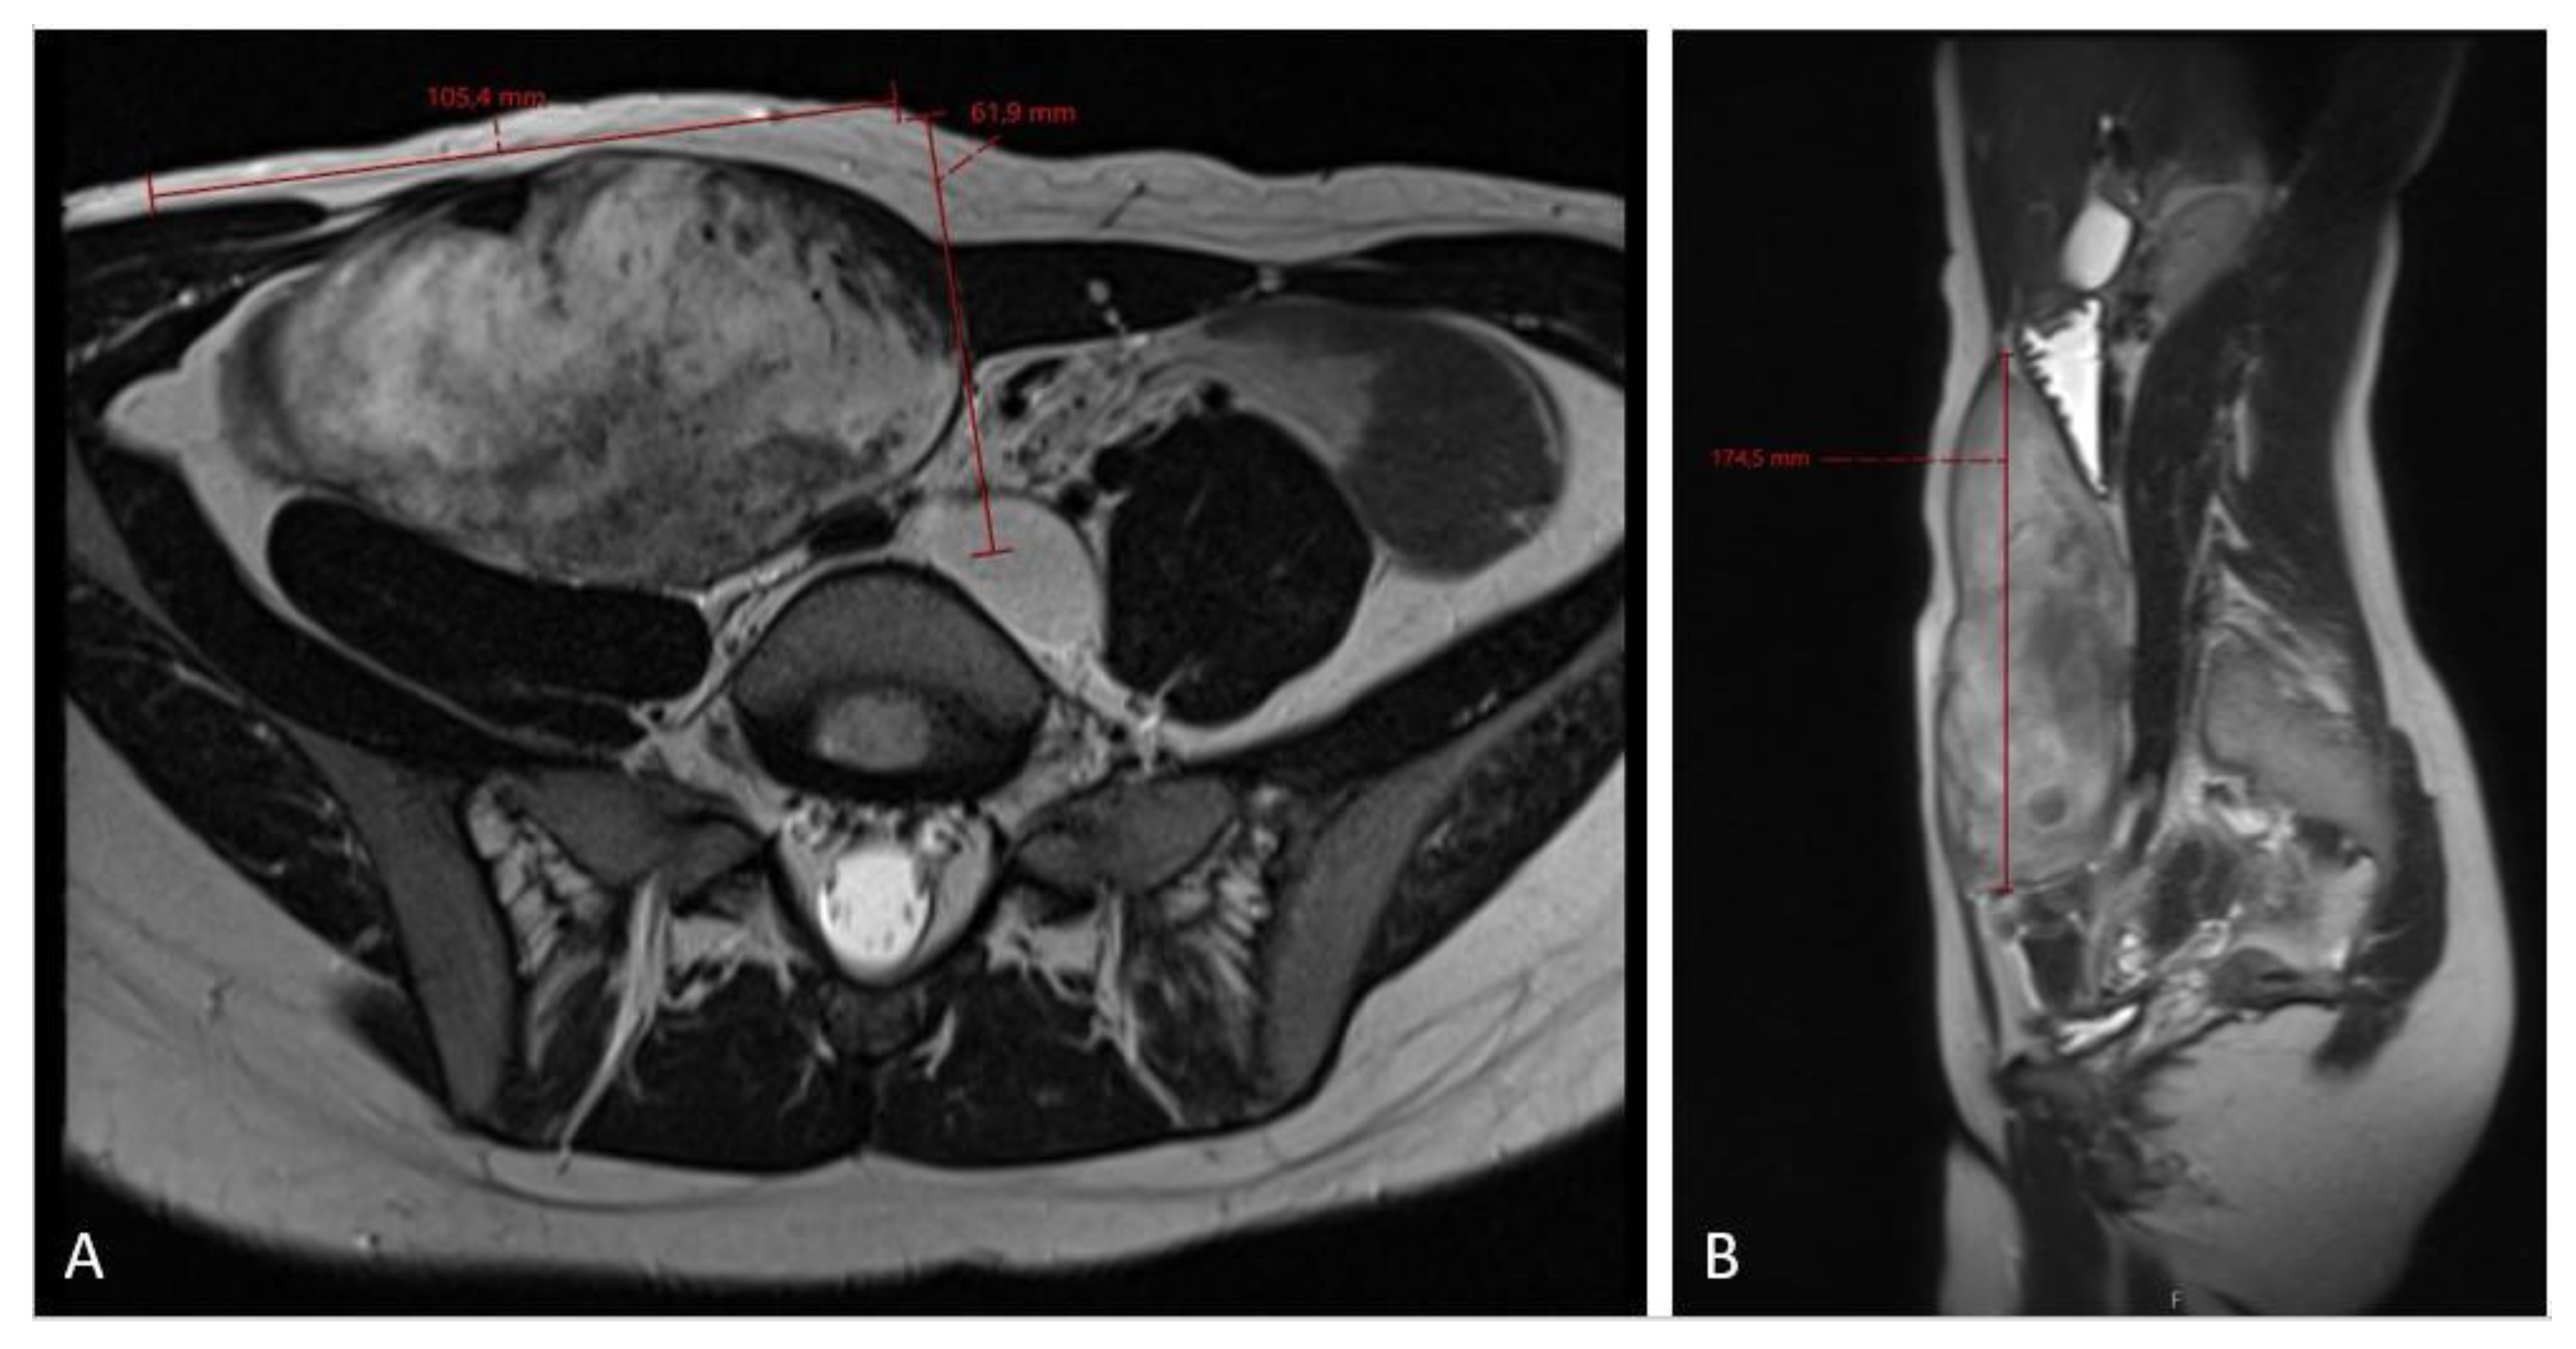

Figure 4.

An MRI scan ((A)—axial plane; (B)—sagittal plane) at the 6-month follow-up checkup showing tumor growth progression, sized 10.5 × 6.2 × 17.5 cm in craniocaudal diameter, located in the musculus rectus abdominis on the right side.

The 3-month MRI control showed a stable tumor size; however, the MRI check at the 6-month follow-up showed significant tumor growth progression (Figure 4), sized 10.5 × 6.2 × 17.5 cm in craniocaudal diameter located in the musculus rectus abdominis on the right side. She was recommended to stop oral contraceptives and preventive devices (IUD) containing estrogen and/or progesterone and was referred to the National Oncology Center for further treatment, where the tumor board determined to administer chemotherapy, and the treatment started with three cycles of Caelyx (doxorubicin hydrochloride), 40 mg/m2 every fourth week, with MRI control afterwards. The patient suffered side effects in form of skin rashes, allergic respiratory problems, and mucositis. She received 60 mg of Caelyx by IV each cycle. The control MRI scan showed no effect of treatment; furthermore, there was a slight progression in the craniocaudal tumor size (12.0 × 6.6 × 20.0 cm), (Figure 5). As the oncologist awaited the latest response to chemotherapy, the further plan was to continue the same treatment options (Caelyx, although at a reduced dose, set to 30 mg/m2) due to the previous side effects. The patient underwent three further cycles with total dose of 47 mg doxorubicin at each cycle. The MRI scan after six cycles showed partial regression of the tumor, now sized 11.2 × 5.4 × 19.1 cm. She was continuously monitored by the surgeon and radiologist with MR scans every 4 months, and the 12-month scan after chemotherapy showed significant tumor regress, sized only 1.2 × 3.7 × 8.7 cm (Figure 6). Five weeks later, the patient became pregnant and was referred from the midwife for gynecological control, starting on week 12 + 4.